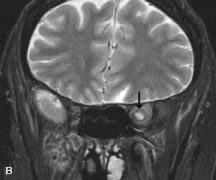

Breast carcinoma metastatic to the orbit has been demonstrated to be hypointense to the surrounding orbital fat on T1-weighted studies and hyperintense on T2-weighted images and has an affinity to the extraocular muscles (Fig. 20).50,64 The MRI characteristics of prostate carcinoma metastatic to the orbit have been described as involving the greater and lesser wing of the sphenoid, orbital roof, and optic canal. Diffuse bone hypertrophy with isointense or slightly hyperintense tissue on T1-weighted images represents the osteoblastic carcinomatous bone infiltration. Contrast enhancement is variable on T1-weighted and fat-suppressed images.65

Fig. 20. A. T1-weighted MR scan demonstrates nodular enlargement of both medial rectus muscles (arrows). B. T1-weighted fat-suppressed contrast-enhanced scan confirms the presence of small metnstatic deposits within the muscles (open arrows).